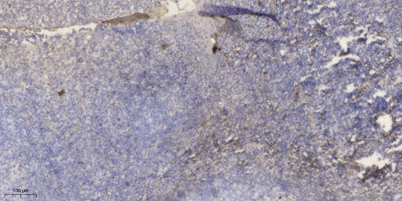

IHC

Recomended Dilution IHC-p 1:50-200, ELISA(peptide)1:5000-20000